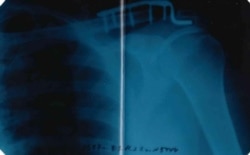

Металлическая пластина в плече, рентген

35-летнего жителя Красноярска Якова в сентябре мобилизовали, несмотря на металлическую пластину на месте травмированного сочленения лопатки и ключицы. В учебной части из-за усиленной нагрузки у него отнялась рука. Возвращать его домой командование отказывается – вместо необходимой операции его угрожают "отправить на спецоперацию".

В начале ноября Якова направили в гражданский травмпункт в Херсонской области, где врач подтвердил, что требуется операция, и выдал справку о необходимости удалить металлоконструкцию.